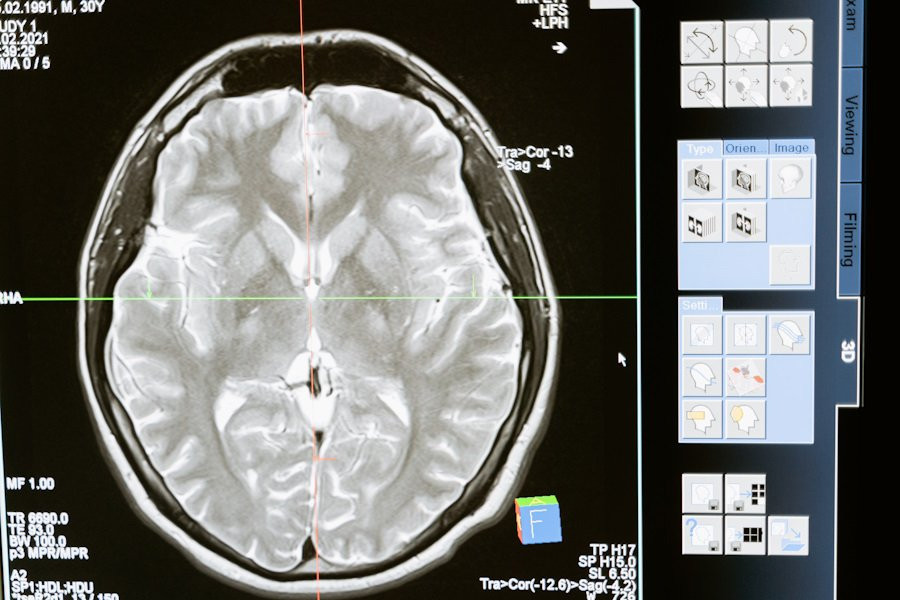

Российские ученые разработали уникальную платформу для борьбы с одной из самых опасных опухолей мозга — глиомой. Этот проект, направленный на улучшение диагностики и лечения, разрабатывается под руководством профессора Галины Павловой в НМИЦ нейрохирургии имени академика Н.Н. Бурденко Минздрава РФ.